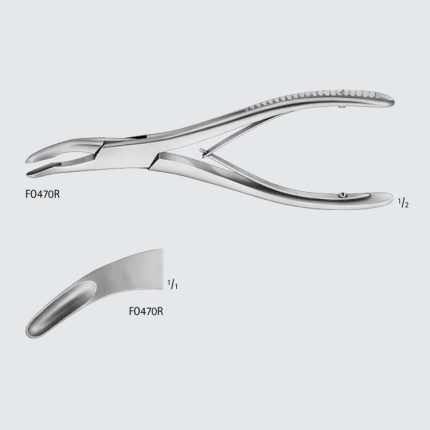

Rongeurs

LUER Bone Rongeur

CatalogNumber Jaw Size(mm) Jaw Length(in.)

FO460R 7.5 x 25 STR 6 7/8

FO462R 9.5 x 33 STR 7

FO411R 4.2 x 20 CVD 6

FO412R 4.2 x 26 STRONG CVD 6 1/8

FO461R 7.5 x 24.5 CVD 6 7/8

FO463R 9.0 x 30 CVD 7